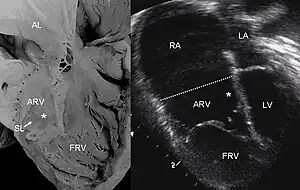

Pathological specimen and ultrasound image of a heart with Ebstein's anomaly: Abbreviations: RA: right atrium; ARV: atrialized right ventricle; FRV: functional right ventricle; AL: anterior leaflet; SL: septal leaflet; LA: left atrium; LV: left ventricle; asterisk: grade II tethering of the tricuspid septal leaflet

The annulus of the valve is still in the normal position. The valve leaflets, however, are to a varying degree, attached to the walls and septum of the right ventricle. A subsequent "atrialization" of a portion of the morphologic right ventricle (which is then contiguous with the right atrium) is seen. This causes the right atrium to be large and the anatomic right ventricle to be small in size.

Anatomic abnormalities

Typically, anatomic abnormalities of the tricuspid valve exist, with enlargement of the anterior leaflet of the valve. The other leaflets are described as being plastered to the endocardium. Tethering the underlying ventricular wall is the most common for the posterior and septal leaflets, and sail-like anterior leaflets may be tethered to the RV free wall also. About 50% of individuals with Ebstein's anomaly have an associated shunt between the right and left atria, either an atrial septal defect or a patent foramen ovale.[4]